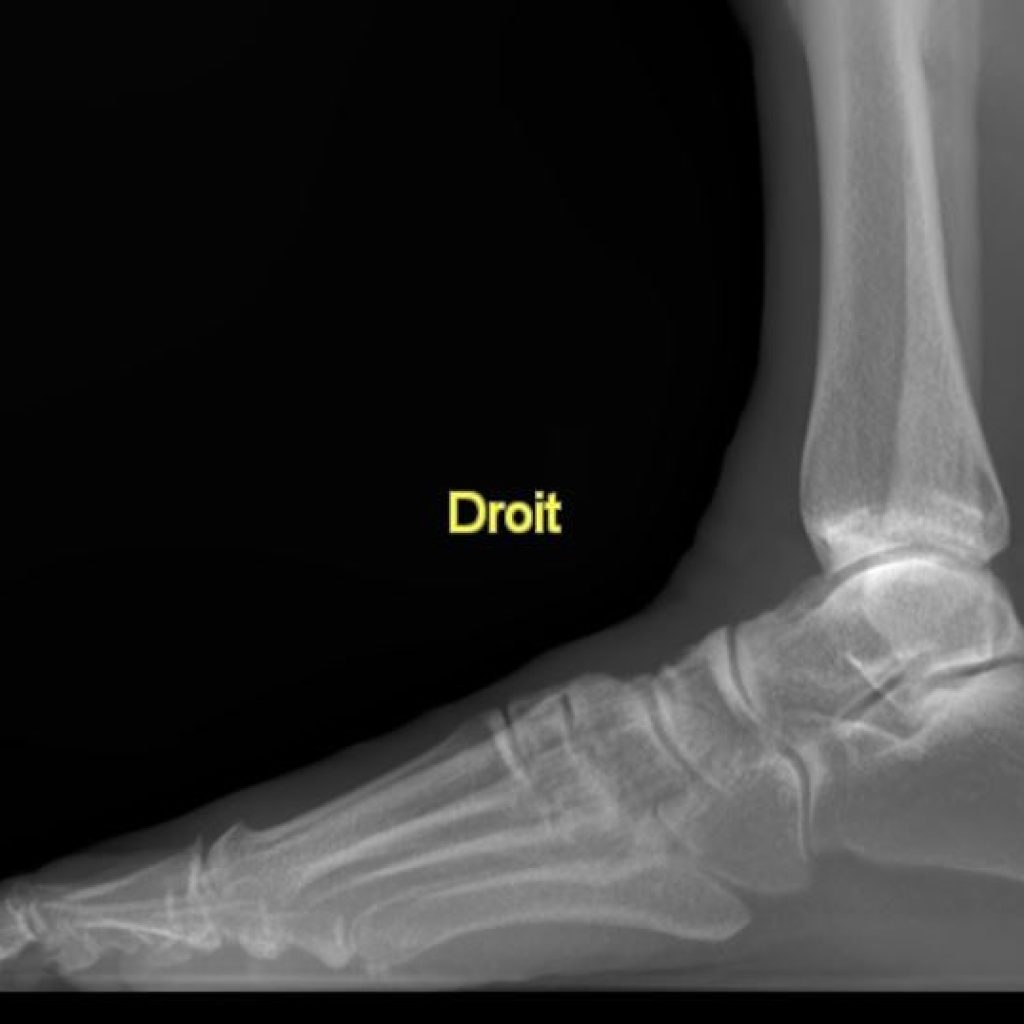

Il s’agit d’un appareil type cone beam permettant d’étudier en position débout, comme un scanner, les pieds, les chevilles et les genoux avec une très faible irradiation du patient comparé à un scanner conventionnel.

Sa finesse d’image lui permet aussi d’être au cœur des bilans traumatiques et rhumatismaux de la cheville et du coup de pied.